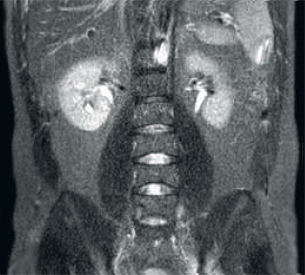

Anderer HF-Empfang

Das Ergebnis: Verrauschte Bilder bei Verwendung identischer Scanparameter